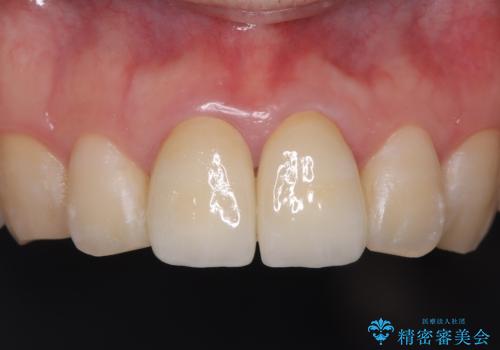

前歯の根のところに違和感がある|根尖性歯周炎|精密根管治療|オールセラミッククラウン|見た目も改善